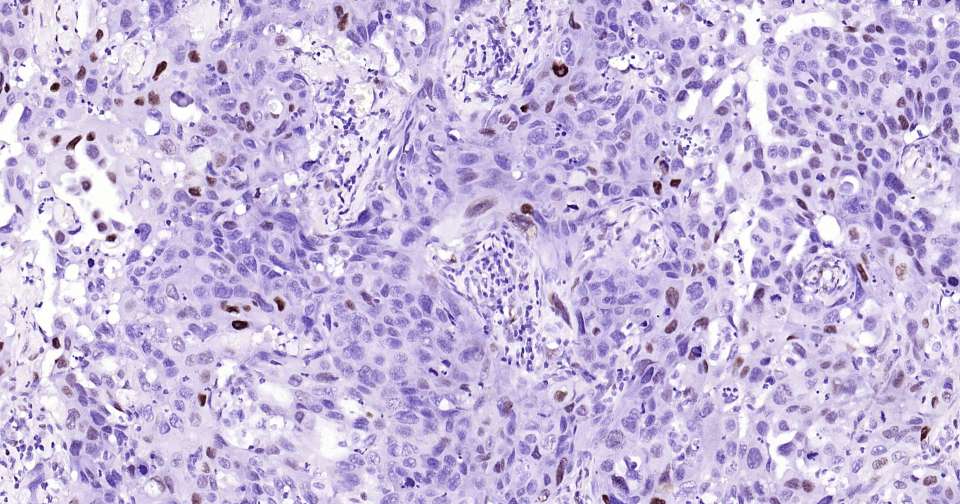

Immunohistochemical analysis of paraffin embedded human lung cancer tissue slide using IHC0357H (Human Phospho-c Jun/JunD (Ser73/Ser100) Kit).